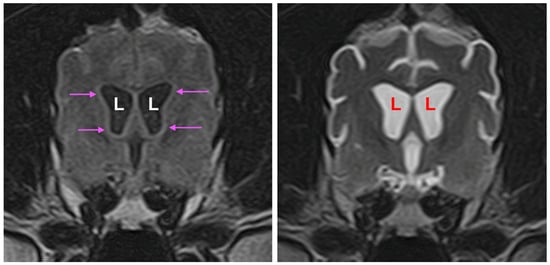

3.1. Disease Phenotype

3.2. Microscopic Findings